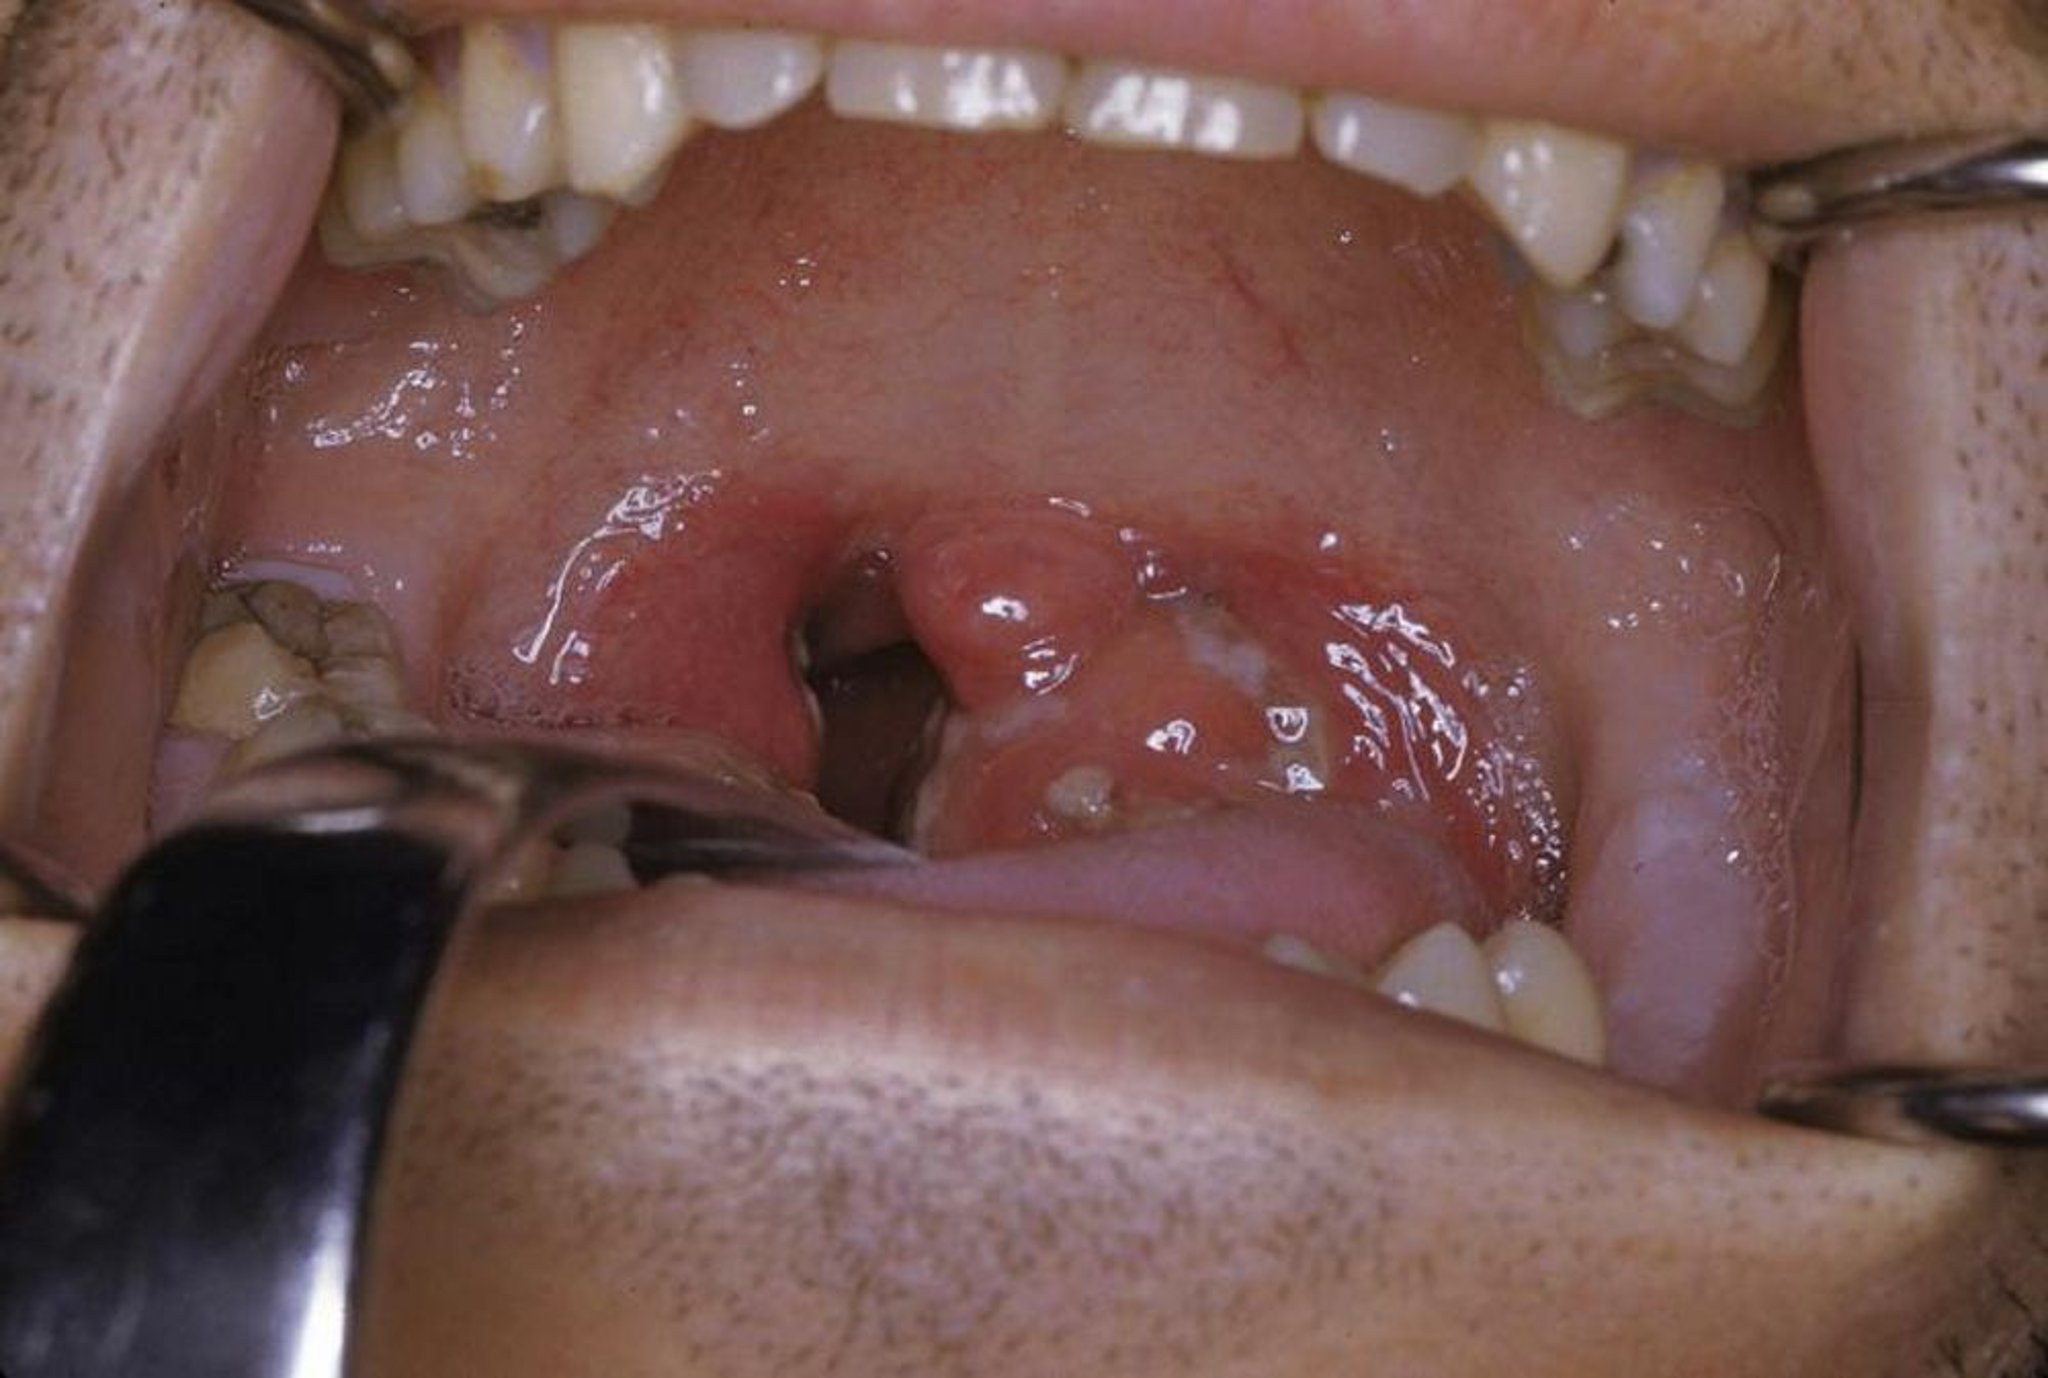

Cette photo montre une amygdalite aiguë avec exsudat et érythème.

Photo fournie par Clarence T. Sasaki, MD.